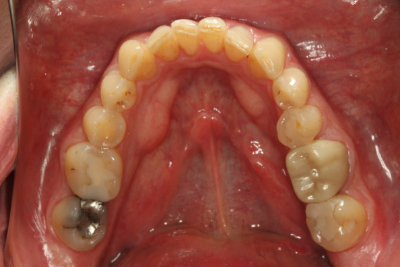

二次元評価から、咬合不安定性の徴候は明らかでした。 ダレンは、切歯縁が非常に薄く、欠け、透明になりつつあるほどでした。 上顎前歯の舌側にはほとんど棚が装着されており、機能的な包絡線が制限されていることが示唆されました。 また、前歯だけでなく後歯にも象牙質への摩耗があり、前歯はクラス1の可動性を持っていました。

審美的には、彼の上顎切歯縁はわずかに垂直方向に欠損しており長さを伸ばす必要がありました。 ダレンは咬合平面がわずかにカントしていましたが、本人はその矯正には興味がありませんでした。 下顎切歯面やアーチフォームも改善が必要でした。

私たちの二次元評価により、マウントされた模型に診断用ワックスアップを行い、三次元治療計画を作成することができました。